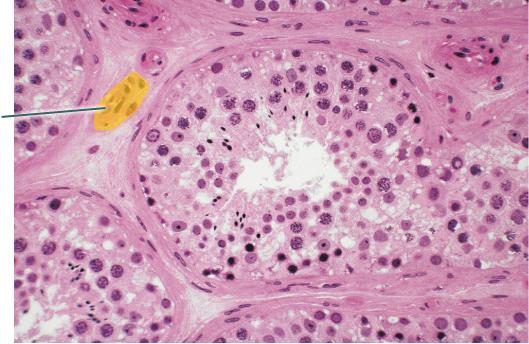

Identify the highlighted cells

Interstitial Cells

Identify the highlighted structure.

Oocyte

What hormone is necessary for the highlighted structure to produce viable sperm?

FSH

Identify the highlighted structure.

Seminiferous Tubules

Identify the highlighted structure.

Sperm